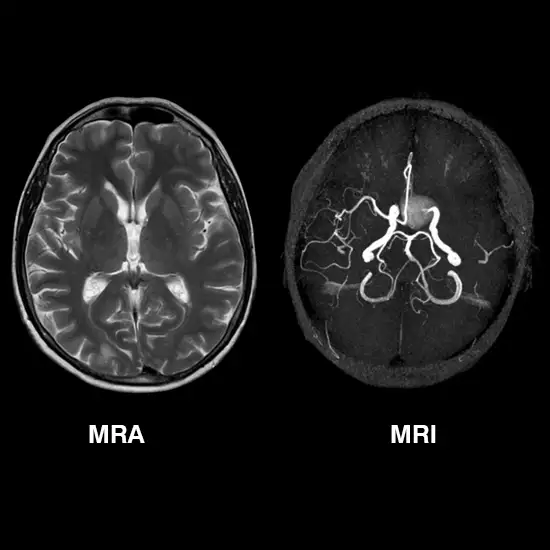

MRI and MRA is a procedure that uses a magnetic field, radio waves, and a computer to produce images of soft tissues, bones, and internal body structures. An MRA of the brain is used to create two three-dimensional images of the blood vessels.

MRA is generally used to analyze the narrowing of the arteries and to rule out aneurysms. It is very significant to remain very still during the scan to obtain the optimal picture quality.